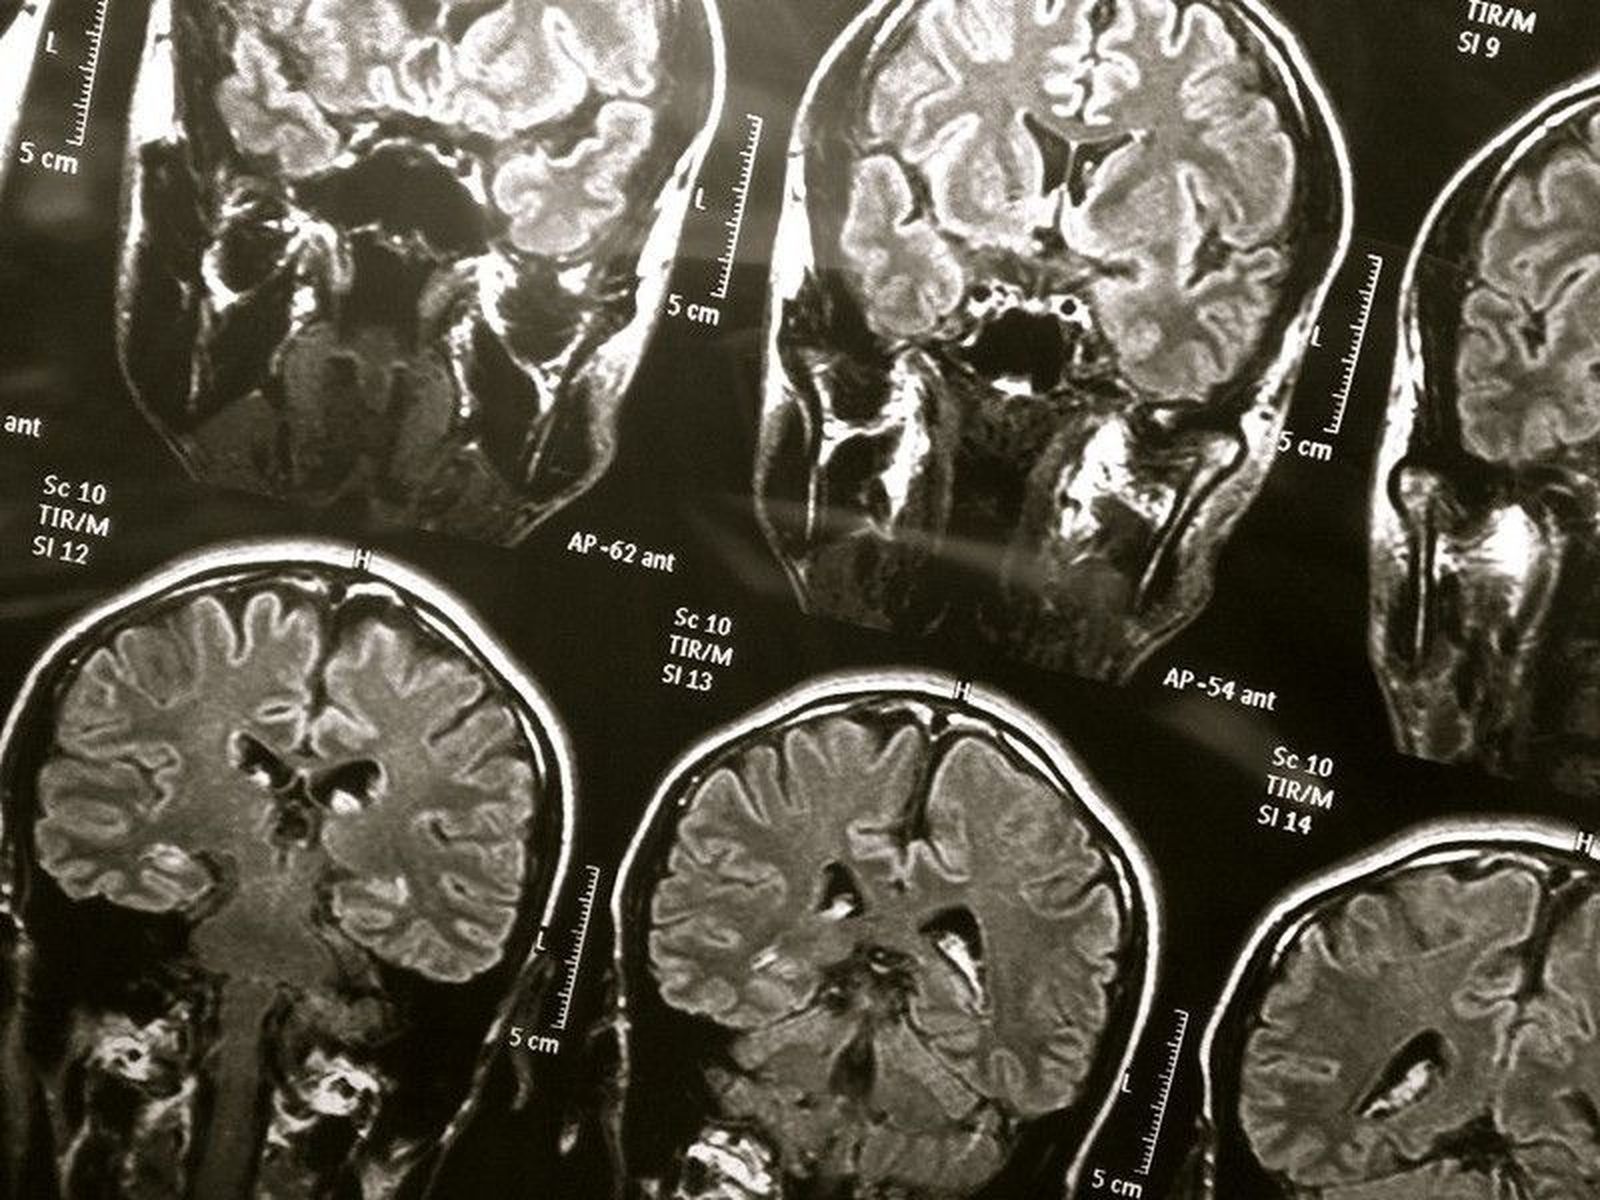

Para aclarar esto, el científico Jack Gallant y sus colegas de la Universidad de California (Estados Unidos) utilizaron imágenes de resonancia magnética funcional para registrar la actividad cerebral de adultos sanos mientras escuchaban o leían una transcripción de un programa de radio.

El equipo de investigación trazó las áreas específicas del cerebro que respondían a cada palabra cuando se leía o escuchaba. La actividad cerebral asociada con cada palabra fue en gran medida consistente en los dos sentidos. Los científicos también pudieron usar datos de un sentido para predecir la actividad cerebral que ocurriría debido al otro sentido.